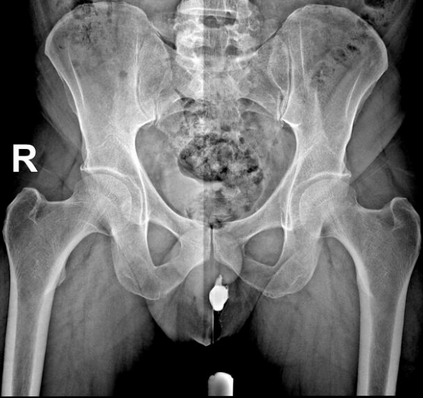

In this study, we aim to initiate the development of Radiology Foundation Model, termed as RadFM.We consider the construction of foundational models from the perspectives of data, model design, and evaluation thoroughly. Our contribution can be concluded as follows: (i), we construct a large-scale Medical Multi-modal Dataset, MedMD, consisting of 16M 2D and 3D medical scans. To the best of our knowledge, this is the first multi-modal dataset containing 3D medical scans. (ii), We propose an architecture that enables visually conditioned generative pre-training, allowing for the integration of text input interleaved with 2D or 3D medical scans to generate response for diverse radiologic tasks. The model was initially pre-trained on MedMD and subsequently domain-specific fine-tuned on RadMD, a radiologic cleaned version of MedMD, containing 3M radiologic visual-language pairs. (iii), we propose a new evaluation benchmark that comprises five tasks, aiming to comprehensively assess the capability of foundation models in handling practical clinical problems. Our experimental results confirm that RadFM significantly outperforms existing multi-modal foundation models. The codes, data, and model checkpoint will all be made publicly available to promote further research and development in the field.